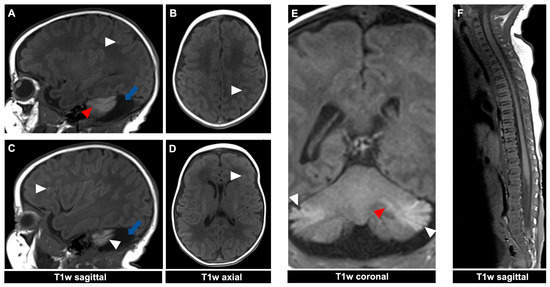

Figure 3.

MR imaging of an 11-day-old female patient with neurocutaneous melanosis (NCM) using an MRI-compatible incubator. (A–D) Imaging findings of leptomeningeal (white arrowhead) and intraparenchymal melanosis (red arrowhead) demonstrate a high T1 signal in sagittal and corresponding axial planes. The image examples illustrate that acquiring two different planes of T1-weighted sequences is advantageous, as it is sometimes difficult to distinguish between leptomeningeal and intraparenchymal manifestations. The patient also has an infratentorial arachnoid cyst ((A), blue arrow). T1w = T1-weighted.